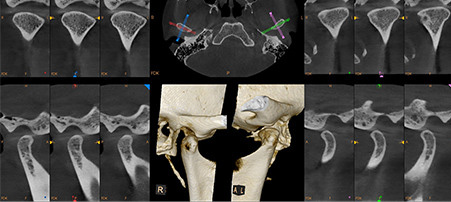

Precision imaging leads to precise treatment. Our cone beam imaging system, which avoids the discomfort of conventional bitewings, offers high-definition anatomical scans. These scans create 3D images of the bones, teeth, nerves, sinuses, and the entire structure of the head, face, neck, and jaw.